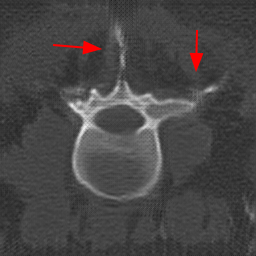

Disentanglement and explicit shape constraints. As shown in Fig. 4, we can see streak metal artifacts nearly everywhere in . M1 can roughly disentangle artifacts and anatomical information but strong vertical artifacts and strange air area appear in (see red arrows of M1 in Fig. 4). For the anatomical structure, M1 learns to segment vertebrae with fully supervised and applied on various CT images, but fails to suppress the false bony structure in and as may misclassify some metal artifacts as bone.

Implicit shape constraints. With , all segmentations are improved with higher Dices and smaller ASDs, see Table 1. As shown in Fig. 4, , and become similar but the high density bone is not correctly segmented in as it maybe treated as metal artifacts. Comparing between M2 and M1, the abnormal air region disappears but metal artifact reduction performance is still not satisfactory.

Anatomy-aware generation. With AADE layer in M3, , and are substantially improved as shown in Table 1. Note, is used as attention map, so we do not expect it to be identical to . In , metal artifacts are further suppressed comparing with M2. Thus, AADE is critical to our anatomy-aware artifact disentanglement framework. With the special structure, can be punished in the image translation and reconstruction processes and the other encoders and generators receive more guidance. However, as shown by blue arrows in Fig. 4, we observe a shadow of vertebra edge of appears in of M3 and the vertebra boundaries get smoothed out in . It may be because sharp edges are encoded as metal artifacts and forced to be added to by artifact consistency loss .

Removal of . To mitigate vertebrae shadows, we remove . The segmentation performance of most images in M4 gets improved because of better synthetic images. Overall, in M4 yields the best segmentation performance for CBCT images with an average Dice of 0.847 and an average ASD of 1.54 mm. For the synthetic images, M4 generates with the best quality and least metal artifacts among all the models. M4 also outputs without vertebra shadows. The results indicate our shape-aware network could preserve anatomical details and transfer the metal artifacts precisely without .